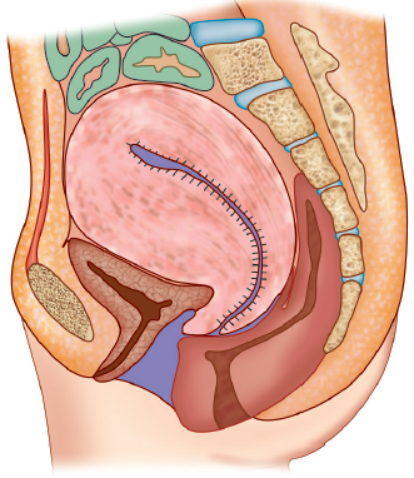

子宫复旧指的是生产结束后,子宫开始恢复到怀孕前的状态,一般要到产后 42 天才能完全恢复。过程中主要涉及到子宫肌肉纤维收缩力的恢复[1-3]。

子宫复旧良好 :产后 1 周子宫缩小到孕 12 周大小(在耻骨联合上方可触及);产后 2 周子宫缩小至盆腔内,在肚子上摸不到;产后 6 周恢复到孕前大小。

子宫复旧不良 :在上述三个时间节点的检查中发现子宫大小仍大于预期,则属于子宫复旧不良[1,2]。

图B. 产后 5 天的子宫示意图